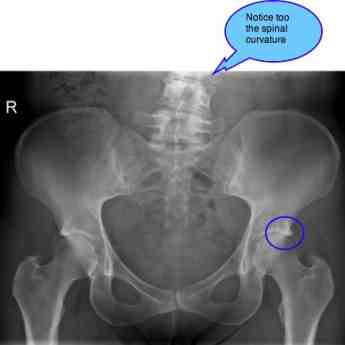

In the following two x-rays you can see a moderately severe case of pincer, in a 58 year old woman.

So too with Femoro Acetabular Impingement Syndrome Pincer. In the above mild case there is minimal hip arthritis. Tthe medical report states: There are no bony abnormalities in the pelvis In reality there is clear evidence of a pincer deformity bilaterally, as well as early sclerotic change in the left sacroiliac joint anatomy.

These are her back X-rays. You can see the scoliosis, and a severely degenerated lumbar joint at L3 - L4.